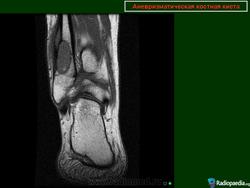

Аневризматические костные кисты.

• Интрамедуллярное эксцентричное метаэпизеальное многокамерное кистозное образование

• В полостях определяются множественные уровни жидкости содержащие кровь

• Ограничены мембраной различной толщины, состоящие из костных трабекул и остеокластов

• В 70% — первичные, без явных причин

• В 30% — вторичные, в результате травмы

• Этиология неизвестна, предполагается неопластическая природа

• Половой предрасположенности нет, в любом возрасте

• Чаще располагаются в длинных трубчатых костях и позвоночнике

Аневризматические костные кисты. Многокамерные кисты с перегородками

• Множественные уровни жидкости

• Склеротическое кольцо по периферии

• При локализации в позвонках – поражает более одного сегмента

• Редко располагается центрально «Раздувает» кость, вызывает деструкцию костных балок, компактного вещества

• Может распространяться на соседние костные элементы